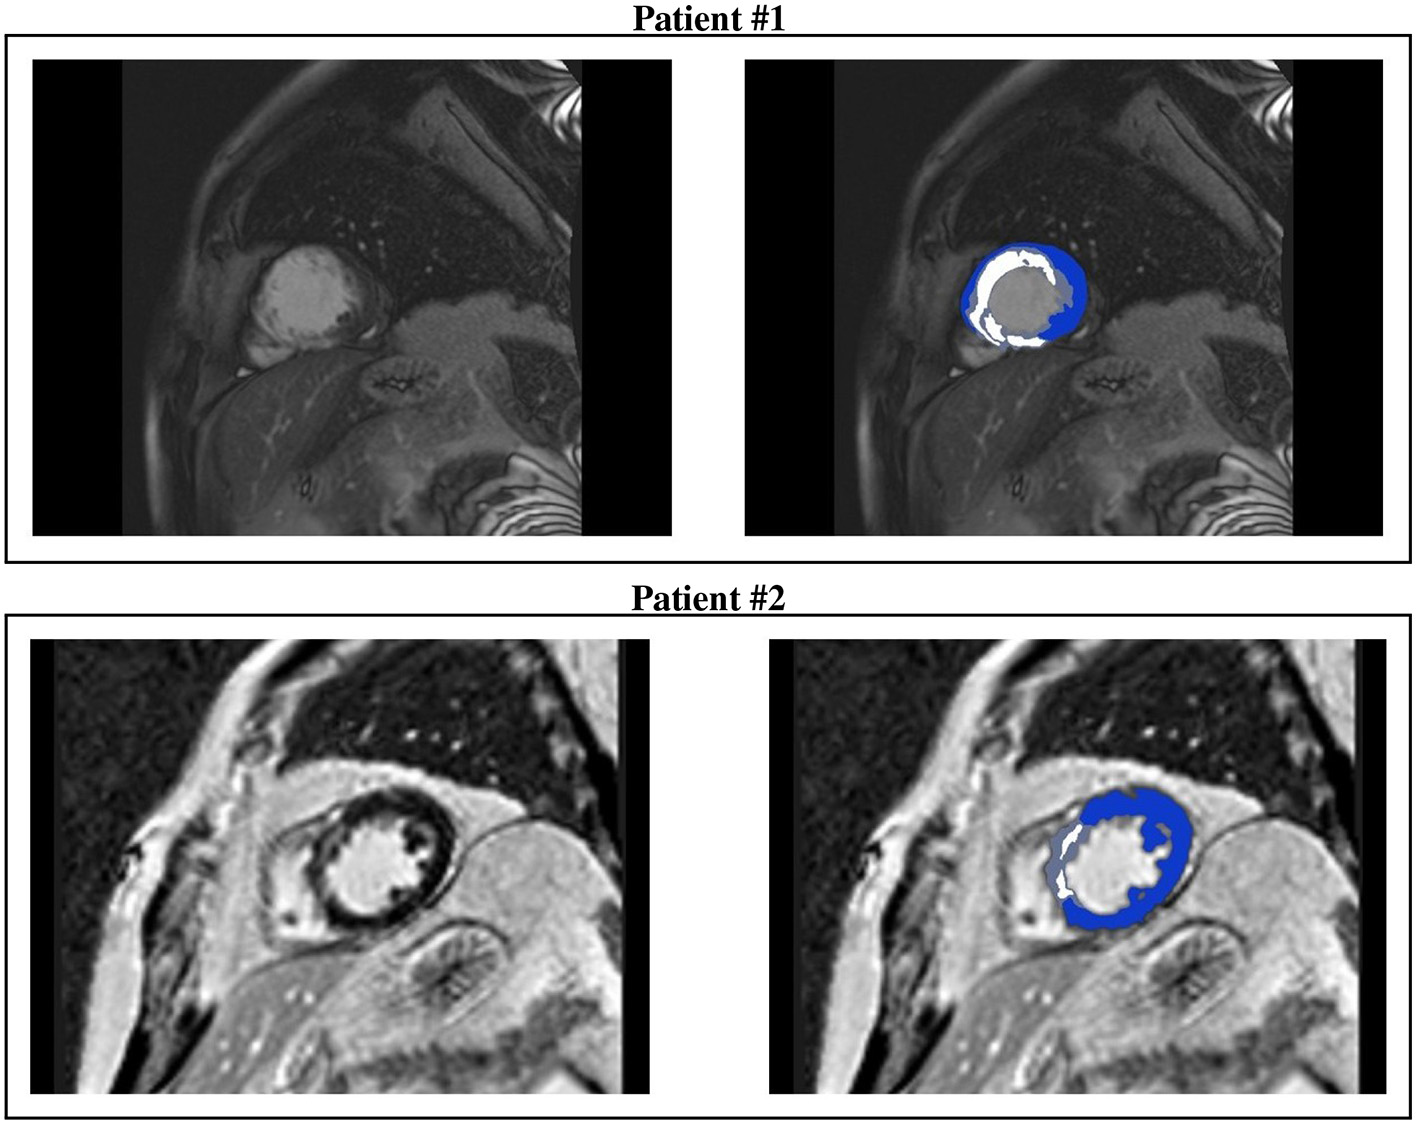

All CMR analyses were performed with Digital Imaging and Communications in Medicine (DICOM) images with a custom software package. Left ventricular volumes, mass, and ejection fraction were quantitatively measured from the stack of short-axis cine images using standard techniques (Rehr et al., 1985; Walsh and Hundley, 2007). Papillary muscles were regarded as part of the ventricular cavity. For each patient, the maximum signal intensity (SI) within an infarct region in each image of the left ventricle stack was automatically determined, and the scar was defined as myocardium with SI > 50% of the maximal SI. A region of interest was then placed by a trained observer in the remote myocardium, i.e., a portion of myocardium without hyperenhancement and with normal motion, in an area free of artifacts and with uniform myocardial suppression. The signal suppression allows the objective spatial extension of the hyperenhancement area. BZ within the infarct periphery was defined as the myocardium with SI > peak remote SI but SI <50% of maximal SI of the high SI myocardium (Amado et al., 2004; Schmidt et al., 2007). The transmural extent of hyperenhancement was measured by standard techniques (Kim et al., 2000). Each short-axis slice was segmented circumferentially into 12 wedges. For each segment, the transmural extent of total hyperenhancement was expressed as a percentage of the total segment area. For each patient, the percentage of segments with transmural extents of hyperenhancement within each quartile (0 to 25%; 26 to 50%; 51 to 75%; or > 75%) was determined. Table 2 summarizes the CMR characteristics of the two patients, see Figures 1, 2.

Figure 2. CMR short-axis slices (left) of interest of patients #1 and #2 and the resulting ventricular segmentation (right) into non-infarcted myocardium (blue), border zone (gray), and scar (white).